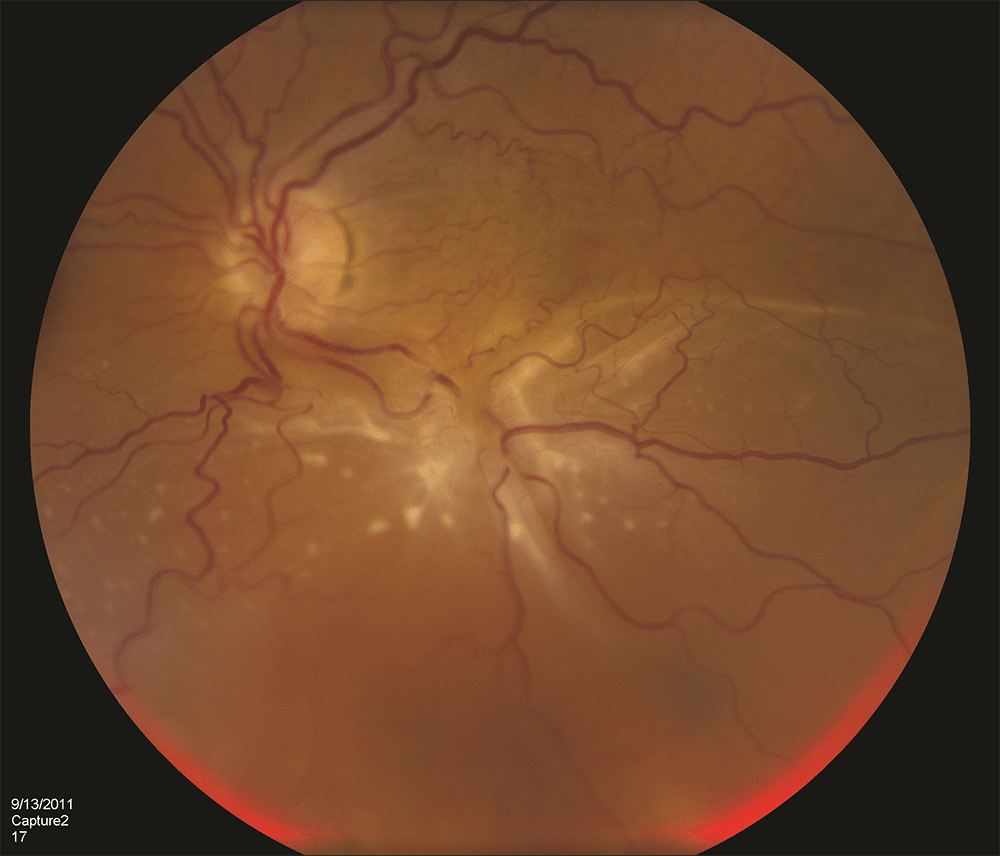

Retinal Detachment an Ocular Emergency Flashes Of Light In The Eye Retinal Detachment This process, known as posterior vitreous detachment, occurs in 90 to 95% of the population. During this separation, the vitreous gel can. Some causes, like retinal detachments, brain injuries or eye injuries, are. You see flashes of light after being hit in the eye or face. Reduced vision, the sudden appearance of dark floating shapes and. Symptoms of retinal detachment. Flashes Of Light In The Eye Retinal Detachment.

Management of retinal detachment a guide for nonophthalmologists The BMJ Flashes Of Light In The Eye Retinal Detachment Flashes of light, known as photopsia, can be an early indicator of retinal detachment and should be treated accordingly. During this separation, the vitreous gel can. Some causes, like retinal detachments, brain injuries or eye injuries, are. Suddenly seeing new floaters and flashes could mean your retina has. Symptoms of retinal detachment can include the following: Reduced vision, the sudden. Flashes Of Light In The Eye Retinal Detachment.